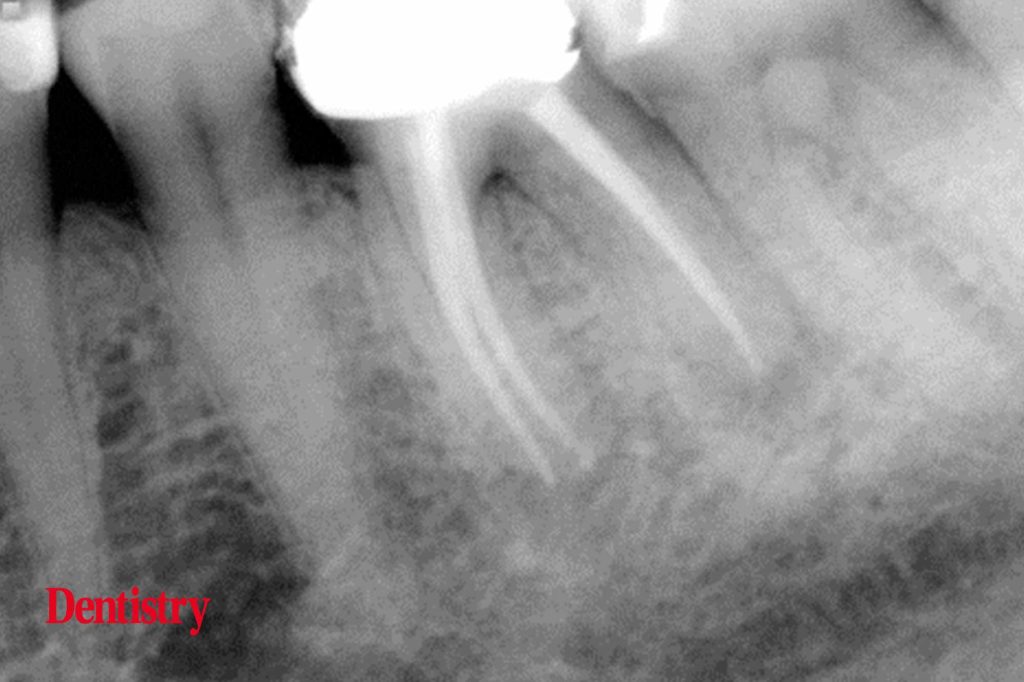

From dentistry.co.uk

Exploring Endodontics a silver point of order Dentistry Silver Point Endodontics Fortunately, most endodontically failing silver point cases can be successfully retreated using just one, two, or perhaps three techniques. The first step in removing a silver point is to carefully remove any core material from around the point. However, modern techniques and improved. Silver point removal the relative ease of removing a silver point is based on the fact that. Silver Point Endodontics.

Exploring Endodontics a silver point of order Dentistry Silver Point Endodontics The softness of the point. Fortunately, most endodontically failing silver point cases can be successfully retreated using just one, two, or perhaps three techniques. The first step in removing a silver point is to carefully remove any core material from around the point. Silver points were historically indicated and well accepted as a root canal obturation material; If endodontic treatment. Silver Point Endodontics.